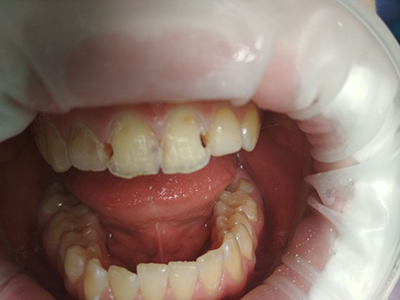

Стоматологи называют кариесом патологию эмали зуба, связанную с уменьшением в ней содержания кальция и сопровождающуюся её разрушением.

Процесс разрушения зубной эмали: что это такое

Кристаллы гидроксиапатита, доля которого в составе внешнего покрытия зуба доходит до 75%, весьма чувствительны к воздействию кислот.

При нарушении кислотного баланса в ротовой полости начинается разрушение и вымывание. Поскольку именно кристаллы обеспечивали твёрдость зубной эмали, с их потерей начинается её размягчение.

Внешне процесс деминерализации — вымывания неорганических веществ — выглядит как белое, шероховатое пятно, которое выделяется на гладкой блестящей поверхности зуба. Если не приняты меры по уменьшению выработки кислот бактериями в полости рта, то происходит дальнейшее нарушение баланса. Бактерии скапливаются в повреждённом месте, так как именно там большая вероятность задержки частиц пищи.

Если не происходит благоприятных изменений, то с увеличением потери гидроксиапатитов органические вещества из пережёвываемой пищи окрашивают пятно в коричневый или бурый цвет.

Внимание! Чем слабее становится защитная оболочка в месте кариозного поражения, тем быстрее начинается разрушение. Под воздействием кислот распространяется кариес как по поверхности, с переходом на другие области, так и вглубь, где под ударом оказывается дентин.